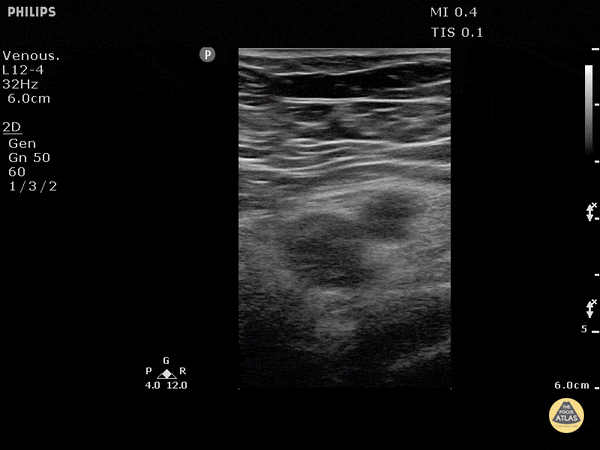

Vascular - DVT Left Common Femoral Vein

Patient with pain and swelling of the entire left lower extremity. Three point POCUS carries a sensitivity of 95% and specificity of 96% for detecting DVT when performed by emergency physicians. Mild external rotation of the hip can help open up the inguinal crease to find the femoral vein. The POCUS should be performed 1-2cm distal to the bifurcation of the common femoral for a complete study. Dr. Justin Bowra et al.